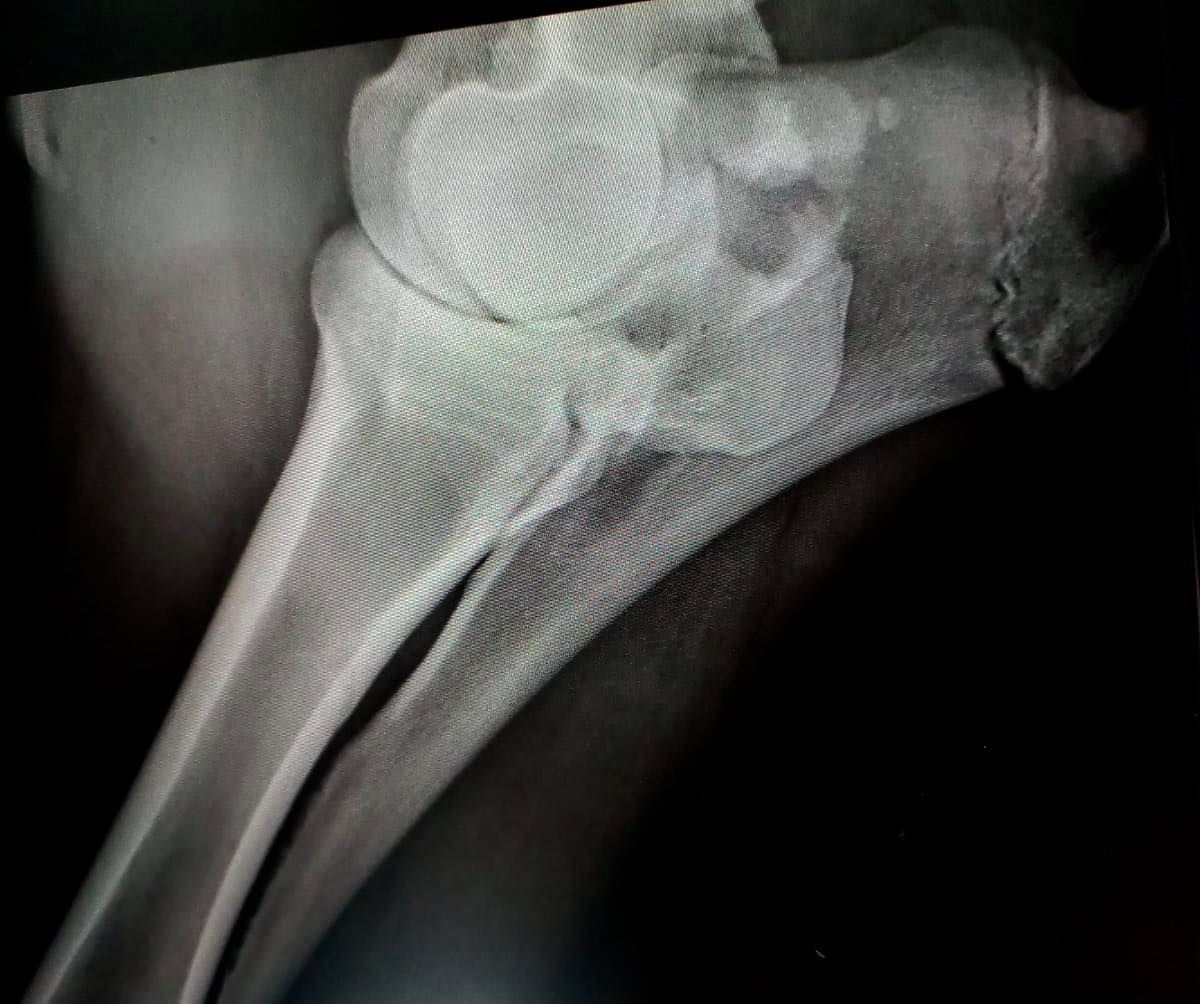

In diesem Monat stellen wir zwei Vierbeiner aus der Nutztierabteilung vor. Es sind Sissi und Vinja. Beide waren auf der Alp, beide haben den Anschluss zur Herde verloren und bei beiden sind die Besitzer zum Entschluss gelangt, sie frühzeitig nach Hause zu nehmen. Gut so, denn obwohl die Rindlein noch ein gutes Stück alleine auf der Alp gelaufen sind, stellte sich bei unserer Untersuchung heraus, dass beide eine Fraktur am Bein aufweisen. Kannst du sie erkennen?

Sissi in der Nähe des Fesselgelenkes (Röntgenbild 1 ) - Vinja am Ellbogen (Röntgenbild 2)

Vinja hat es weiter oben erwischt, nämlich am Ellbogen. Hast du das abgesprengte Teil erkannt? Hier handelt es sich um eine sogenannte „Avulsionsfrakrur“. Das spezielle daran: Sie entsteht durch übermässigen Zug an einem Band und wird deshalb auch als knöcherner Bandausriss bezeichnet.